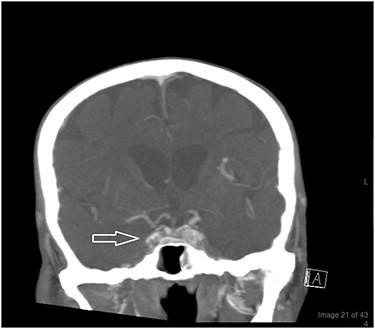

The patient was promptly started on intravenous meropenem, vancomycin and heparin. The next day, the patient’s level of consciousness deteriorated; he developed seizures and orbital involvement of the infection worsened. A CT brain venography revealed poor enhancement of the right cavernous sinus (Fig. 3). A lumbar puncture sample was later found to be negative for microorganisms. The patient was evaluated by an ear–nose–throat (ENT) specialist who made a provisional diagnosis of mucormycosis due to the presence of micronasal abscesses and right alar blackish discoloration. Intravenous amphotericin B and caspofungin were added to his treatment.

A CT brain venography revealed poor enhancement of the right cavernous sinus (white arrow) the following day. His sinuses were initially clear but later showed partial opacification of the maxillary and sphenoid sinuses with fluid levels denoting acute insult. Increased right pre-septal thickening and abnormal infiltration of the right eye were noted as well.